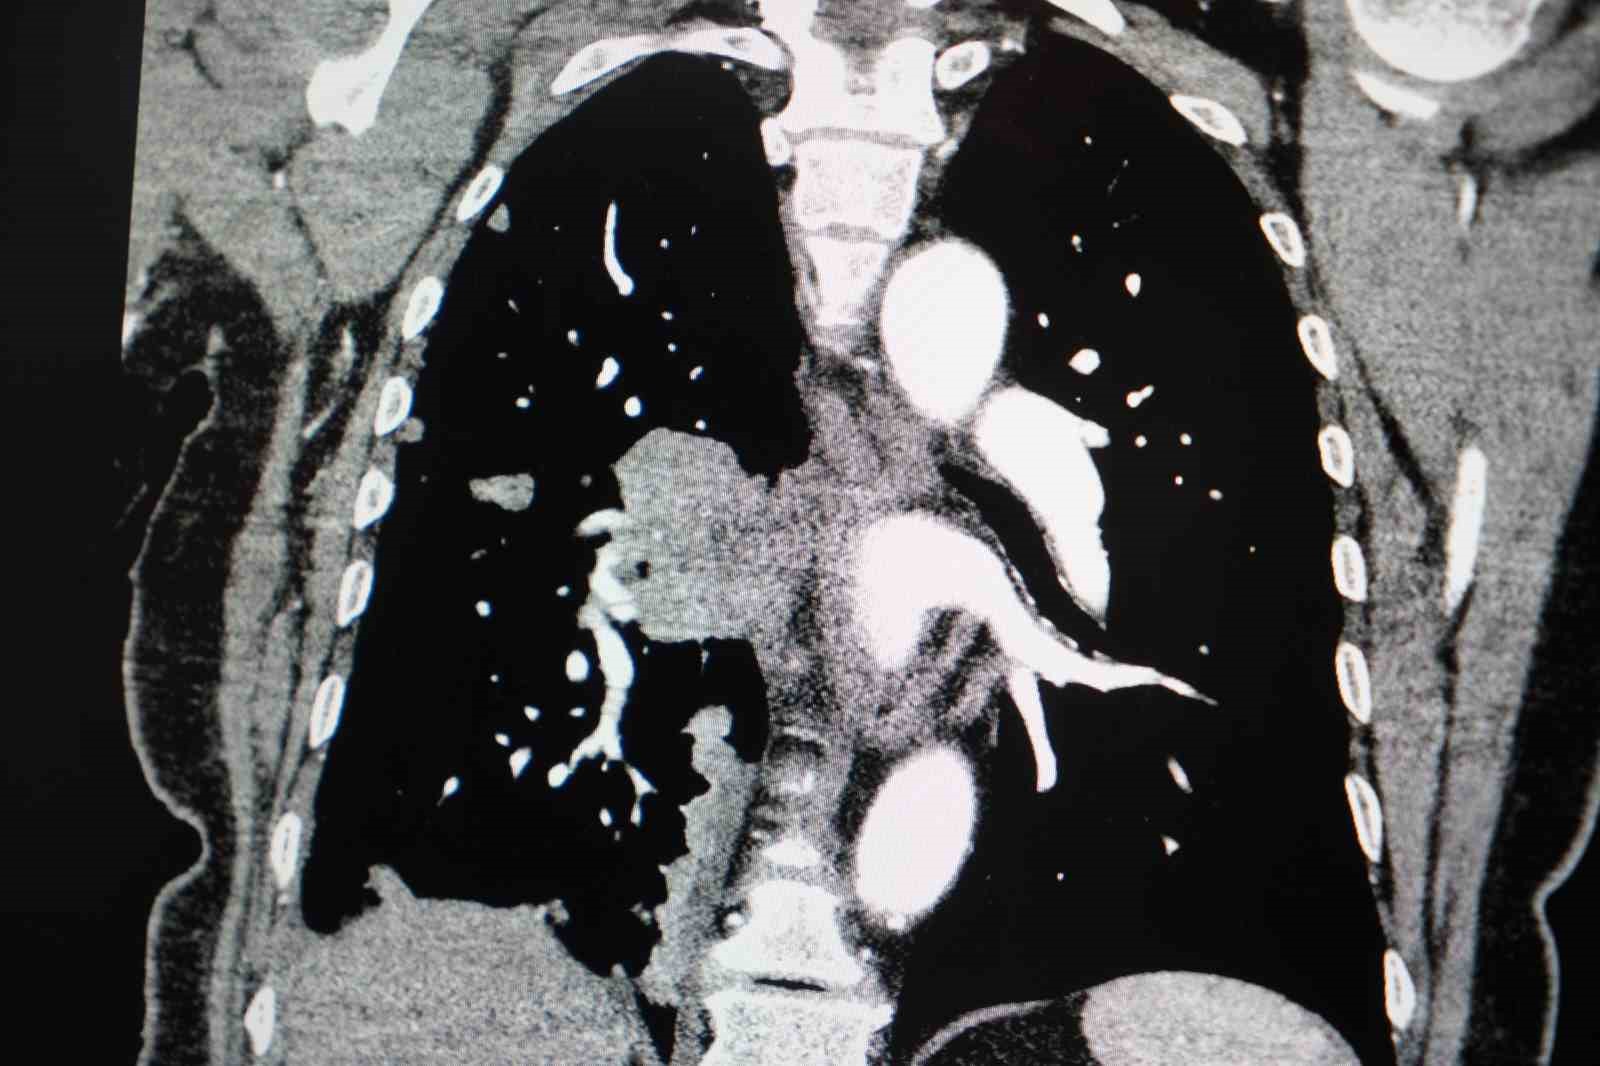

Akciğer kanseri vakalarındaki artışa da dikkat çeken Özkaya, "Son yıllarda hem sigara içen hem de hiç sigara kullanmamış bireylerde akciğer kanseri vakalarında dikkat çekici bir artış görüyoruz. Özellikle kadınlarda adenokarsinom tipi akciğer kanseri belirgin şekilde artış göstermektedir., Yapılan son araştırmalara göre akciğer kanseri teşhislerinin yaklaşık yüzde 20’si hiç sigara içmemiş bireylerde konuluyor. Bunun en önemli nedeni pasif içiciliktir. Yani siz sigara içmeseniz bile, yakın çevrenizde sigara içiliyorsa akciğer kanseri riskiyle karşı karşıya kalabilirsiniz" ifadelerini kullandı.

Sigaranın kadın sağlığı üzerindeki etkilerine değinen Prof. Dr. Özkaya, "Sigara kullanımı kadınlarda sadece akciğer kanseri riskini değil, kalp krizi riskini de ciddi şekilde artırmaktadır. Ayrıca gebelikle ilgili sorunlar, bebek sağlığı problemleri ve rahim ağzı kanseri gibi cinsiyete özgü hastalıklar da sigarayla doğrudan ilişkilidir" dedi.

"Sigara içen kadınlarda, kanserle ilişkili bazı gen mutasyonlarını erkek içicilere göre daha sık görüyoruz. Bu nedenle kadınlarda sigara kullanımı, çok daha dikkatle ele alınması gereken önemli bir halk sağlığı sorunudur."